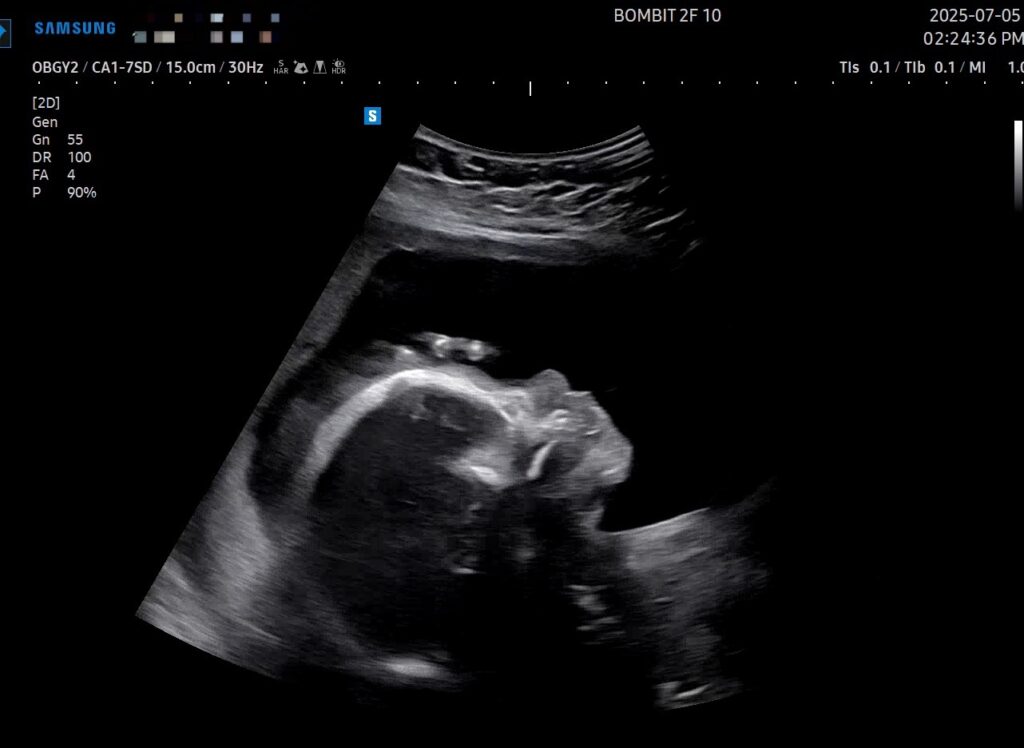

이건 초음파 사진!

초기 때는 초음파 옆모습 단면이 아기처럼 예쁘게 보였는데, 전반적인 크기가 커지면서 눈두덩이랑 턱뼈가 초음파로 적나라하게 드러나게 되었다. 그래서 초음파 사진이 약간 괴기스러워졌다..ㅋㅋㅋ